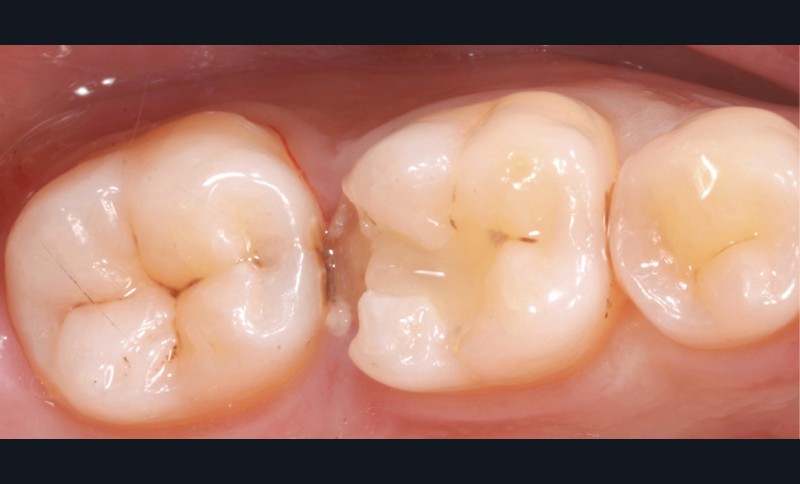

Lors de la préparation d’une cavité pour inlay/onlay, il est fréquent d’être confronté, en fin de nettoyage, à la présence d’une ou plusieurs parois résiduelles dont la résistance mécanique paraît douteuse du fait de leur localisation ou de leur épaisseur. Les parois épaisses (+ de 2 mm) peuvent généralement être conservées (cas clinique 1) et les parois fines (- de 1 mm) doivent généralement être recouvertes. Un inlay (en composite ou en céramique) est alors réalisé. Il doit avoir lui même, au final, une épaisseur globale minimale de 2 mm pour assurer sa résistance mécanique intrinsèque à la mastication. Si un recouvrement cuspidien est indiqué, la réduction occlusale doit donc se faire sur 2 mm de hauteur au minimum [1, 2].

S’il est impossible de connaître avec certitude le risque de fracture d’une cuspide, l’objectif de cet article est de donner des éléments objectifs de prise de décision de la conservation ou du recouvrement des parois d’épaisseur moyenne à la fin du nettoyage cavitaire selon la dent, l’occlusion, la forme et le volume de la cavité, la présence ou non de dentine, la vitalité ainsi que l’incidence esthétique.

La localisation (type de dent)

Le pronostic clinique semble plus favorable pour les prémolaires que pour les molaires [3-5], car une plus grande résistance est généralement nécessaire pour les parois des molaires. Mais si 75 % des fractures à la mandibule affectent les molaires, et plus particulièrement la première molaire, au maxillaire, les fractures se répartissent équitablement entre le secteur molaire et le secteur prémolaire [6]. L’épaisseur de l’émail, la largeur de la cuspide comme les…